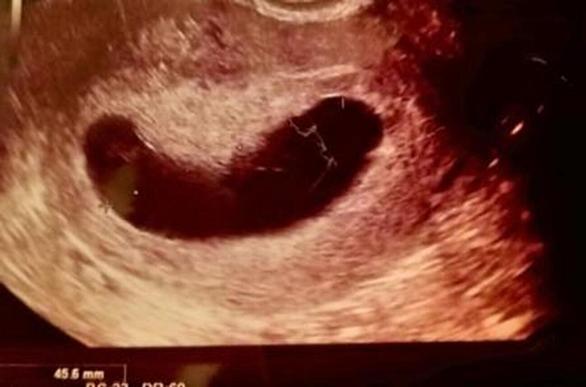

私は現在妊娠6ヶ月目に突入している。 5月にベビたんが誕生する予定。 最近はベビたんの胎動を感じるようになってきて、ポコンポコンとお腹が動くのを見て 「生きてる」 と安心する毎日。 1度目の妊娠 実は今回の妊娠は私の人生2度目の妊娠。 出産経験はゼロ。 つまり、1度目の妊娠は流産だった。 夫と付き合い始めて約4ヶ月後、初めての妊娠がわかった。 その時まだ 「この人と結婚するんだ」 と心底思って付き合っていたわけではなかったから、突然の妊娠発覚に正直戸惑った。 嬉しい気持ちもありつつ驚きもあり、そして何よりも結婚の話なんて全くしてない人に妊娠報告をしてどんな反応が返ってくるのか不安で堪らなかった…